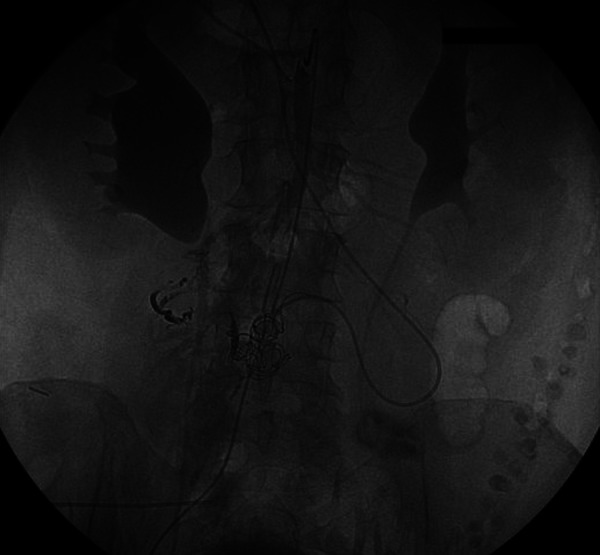

Figure 3.

Coiling of the draining vein. Note is made of glue going into the nidus from the arterial side.